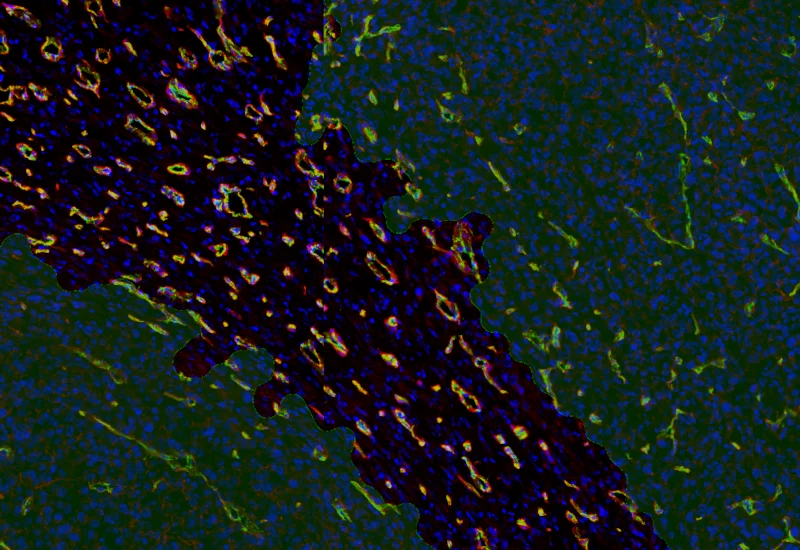

Original Image

Combined detection